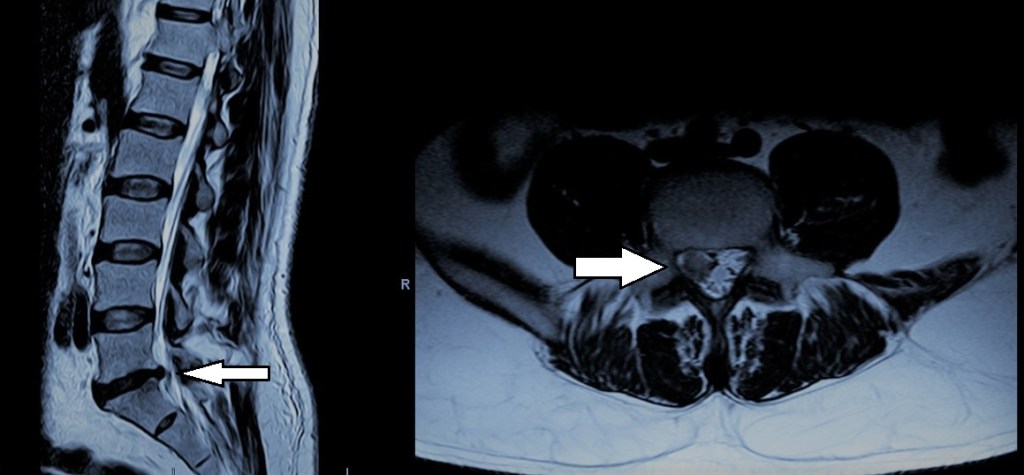

Constituye la causa más frecuente de lumbociática en personas entre 20 y 60 años. Se produce debido a la degeneración del disco intervertebral, lo que da lugar a una rotura de su anillo fibroso y al desplazamiento posterolateral del material discal que provoca una compresión de las raíces nerviosas que interesan a la extremidad inferior. Nos referimos a protrusión cuando existe un desplazamiento global del disco sin que llegue a tener lugar la herniación del mismo ni la repercusión sobre estructuras nerviosas. Tanto hernias como protrusiones aparecen con mayor frecuencia en los segmentos L4-L5 y L5-S1. La sintomatología típica cuenta con una fase incial en la que tiene lugar un dolor en la región lumbar que después pasa a irradiarse a una de las extremidades inferiores a través de la región glútea, cara posterior del muslo y cara lateral de la pierna.